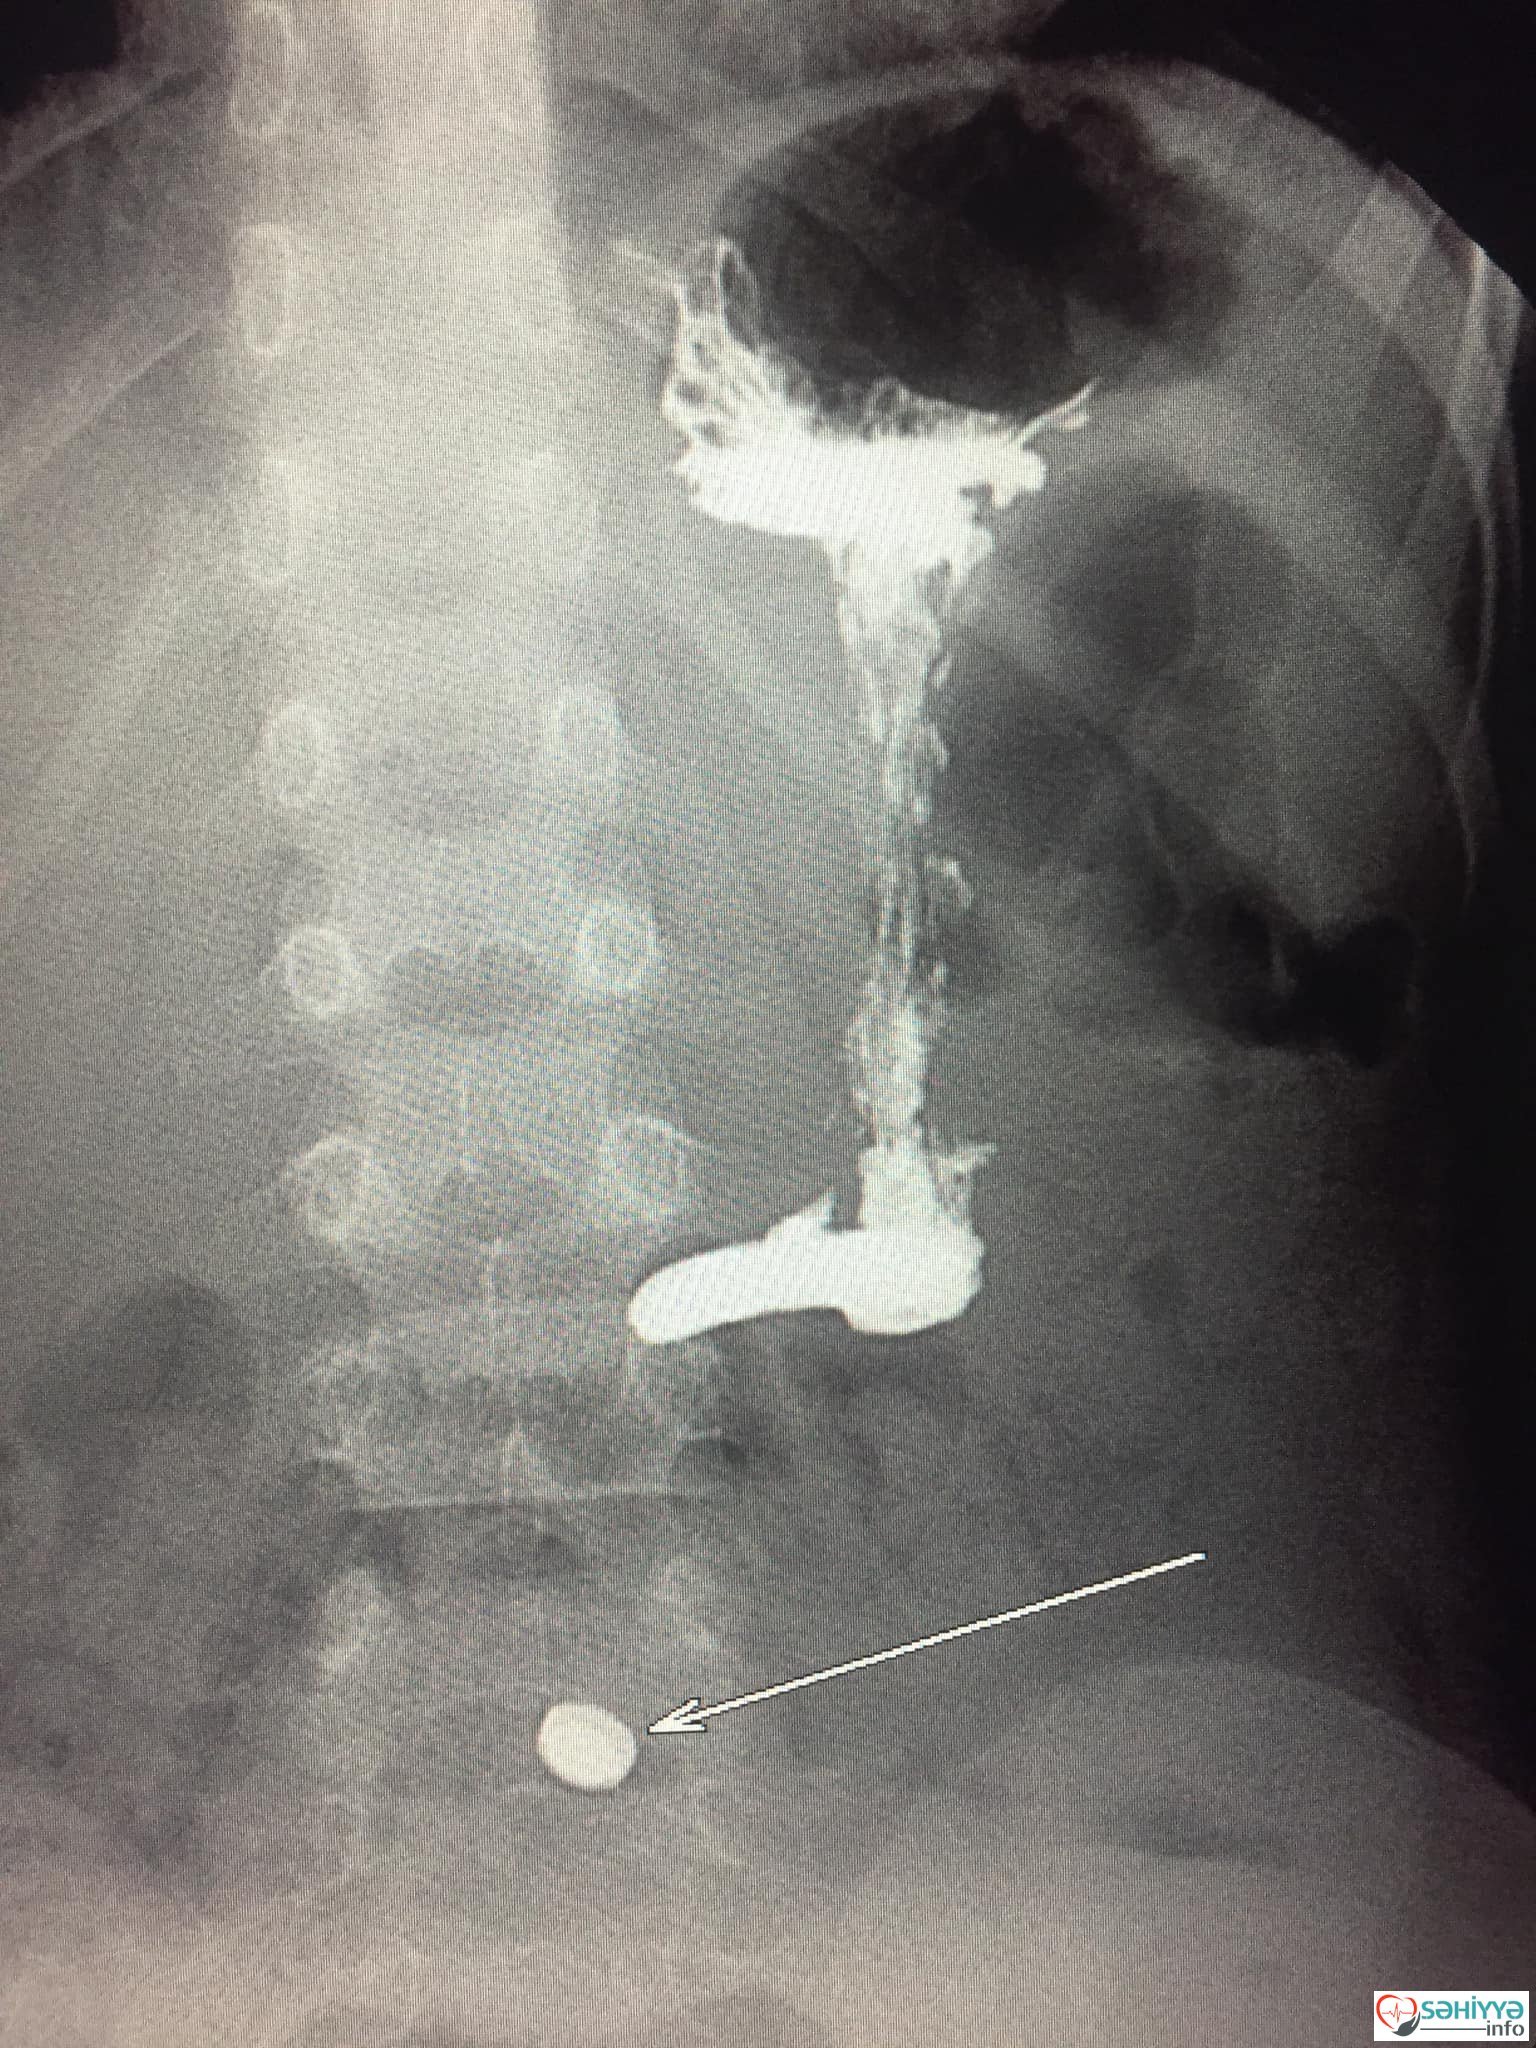

Sehiyye.info xəbər verir ki,Lent.az-ın məlumatına görə, paytaxtda yerləşən özəl xəstəxanalardan birinə gətirilən 4 yaşlı uşağın nazik bağırsağında metal yad cisim tapılıb. Uşağın müayinəsi zamanı həkimləri heyrətə gətirən fakt ortaya çıxıb.

Belə ki, həmin azyaşlının nazik bağırsağında batareya aşkarlanıb. İlkin məlumata görə, azyaşlının həmin batareyanı udduğu ehtimal edilir.